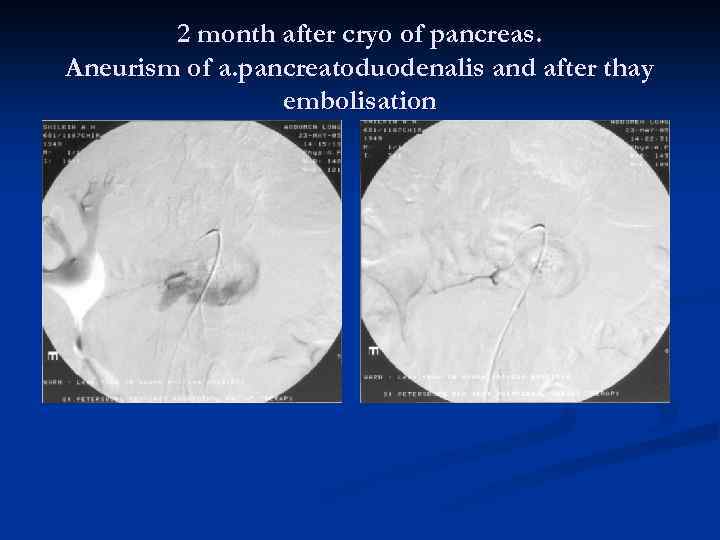

2 month after cryo of pancreas. Aneurism of a. pancreatoduodenalis and after thay embolisation

2 month after cryo of pancreas. Aneurism of a. pancreatoduodenalis and after thay embolisation